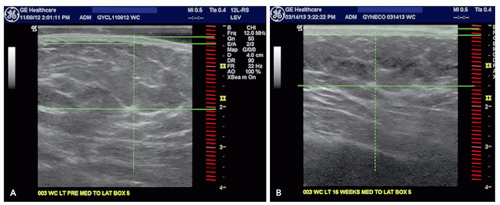

![]() FIGURE 6.1.1 Example of ultrasound measurement of fat reduction before treatment (A) and 4 months after (B). Note reduction in the thickness of the adipose layer. |

Ultrasound. Ultrasound has been validated as the most accurate and reproducible method for measuring adipose layer thickness following nonsurgical fat reduction11,12 (Figure 6.1.1). Ultrasound measurement reproducibility is very high for both subcutaneous and intra-abdominal fat thickness and highly correlated with CT adipose tissue determinations.